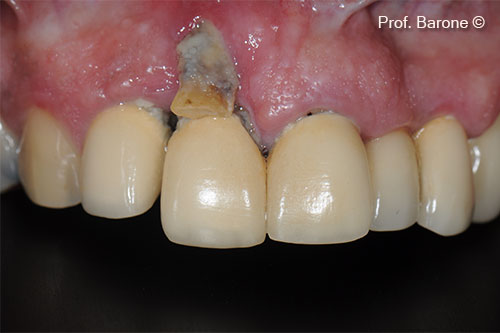

Final Crown